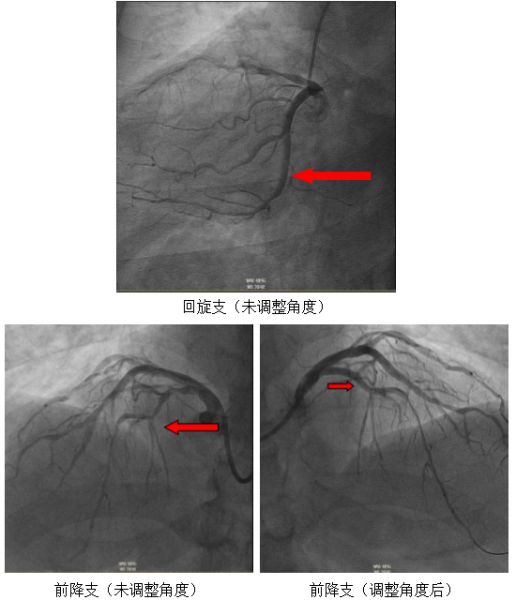

团队创新性地调整了DSA大型C形臂的投照角度,模拟特殊的“俯位”投射。通过让机臂围绕患者进行一系列适配性角度的投照,从特定方向采集图像,从而在源头上获取更易于解读的原始影像。这一调整使医生能够运用最熟悉的解剖思维进行手术,显著缩短了术中判断与操作的时间。

病变精准显影:得益于设备特殊投照与影像反转技术,患者的冠状动脉树在屏幕上清晰、直观地展开。造影结果显示,其前降支的走形与空间分布与正常人完全一致,但近段存在重度狭窄。